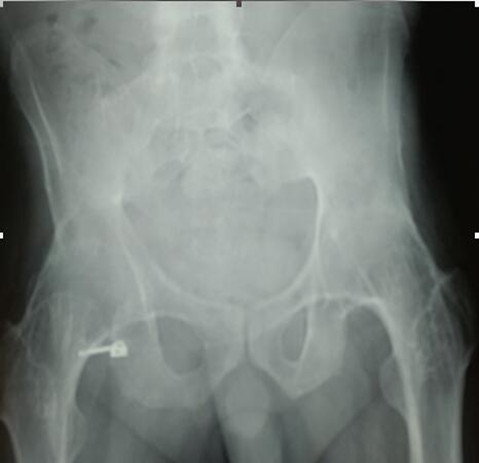

强直性脊柱炎、双侧股骨头坏死、

双侧髋关节融合患者的双侧全髋关节置换术

刘先生29岁,于十余年前无明显诱因出现浑身乏力、消瘦、背部肌肉僵硬,晨起明显,活动后缓解的症状,随着病情逐渐发展,出现腰骶部坚硬感,间歇性出现腰痛和两侧臀部疼痛,放射至大腿,经多方诊治,最终确诊为强直性脊柱炎。由于刘先生的病情迁延不愈,双侧髋关节疼痛愈发严重,于是前往当地医院检查治疗,诊断为双侧股骨头无菌性坏死,自行保守治疗。6年前逐渐出现双侧髋部旋转及屈伸活动障碍,严重影响日常生活。3年前开始出现颈部僵硬,活动受限,保守治疗多次均未好转。为求进一步诊治,刘先生及其家人来到了骨外一科。经过仔细查体及辅助检查,刘先生被诊断为:强直性脊柱炎、双侧股骨头坏死、双侧髋关节融合。白玉江主任建议其做:双侧全髋关节置换。经过3个小时的手术,刘先生的双侧全髋关节置换手术顺利完成,目前,刘先生恢复良好。

手术难度:因患者双髋关节融合,无活动度,大大增加手术操作难度,又因肺功能略差,全麻插管难度大大提高,麻醉科张宏伟主任行纤维气管镜清醒插管,手术顺利。

术前X线